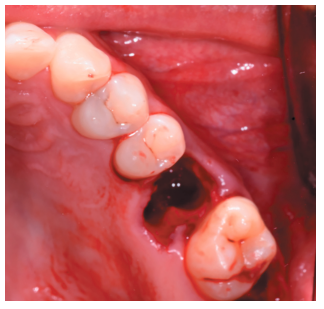

Tras obtener el consentimiento informado, se realizó un bloqueo anestésico mediante Articaína al 4% con adrenalina 1:100.000 (Ultracain®, Normon SL, Madrid, España) del nervio alveolar superior posterior y medio, y palatino anterior. Se realizó la extracción de forma atraumática de los restos radiculares del 2.6 y el legrado del proceso apical (Figura 6), dejando el alveolo del 2.6 preparado para recibir el autotrasplante del 2.8 (Figura 7).